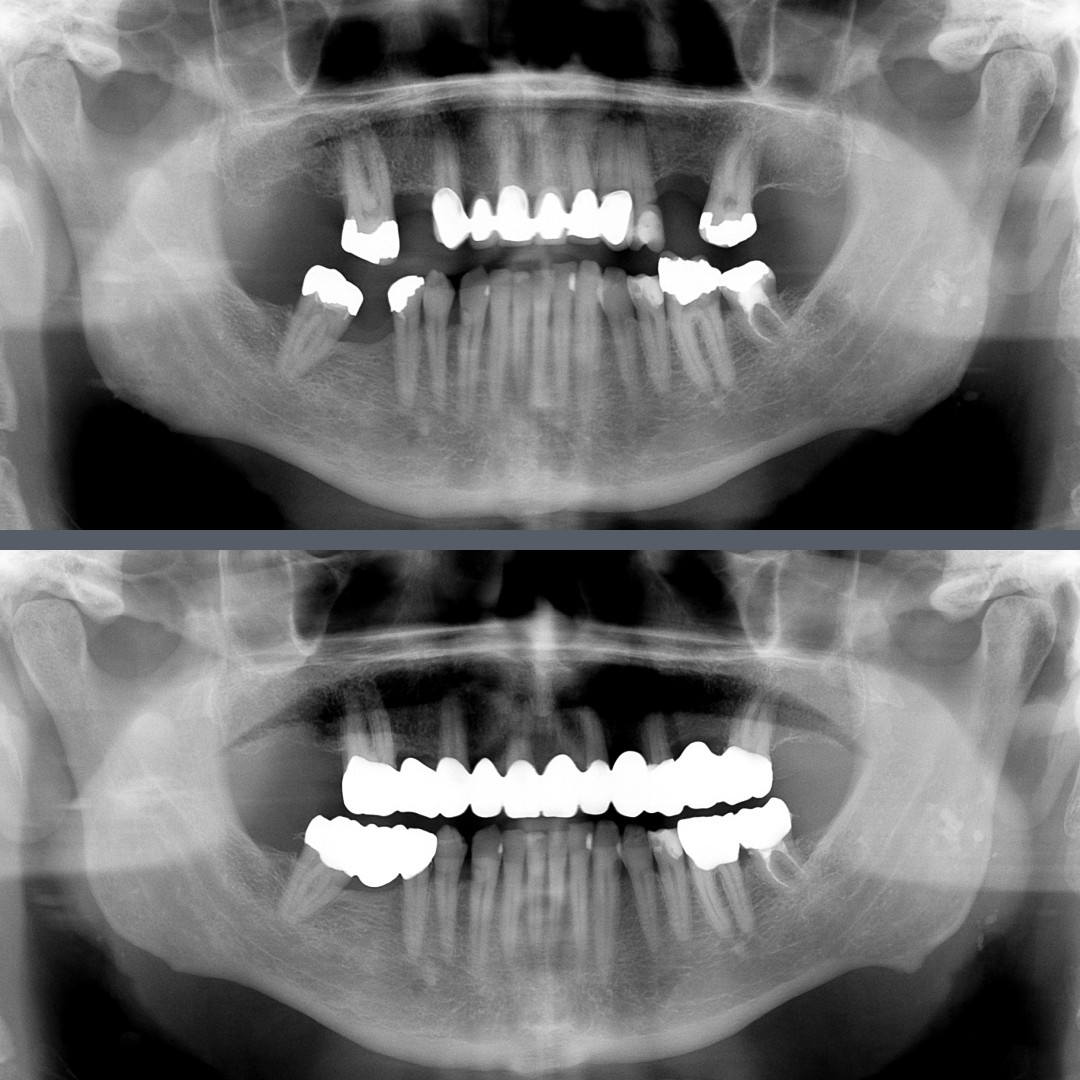

Aesthetic Smile Rehabilitation and Bite Correction with Zirconia Restorations

The Dental Problem

The 66-year-old male patient presented with a complex dental condition.

His teeth had not only lost their aesthetic appeal – the combination of missing teeth and the compromised condition of the remaining ones had also led to a misaligned bite and reduced chewing function. Our goal was to create an aesthetic smile while restoring proper bite alignment and optimal chewing.